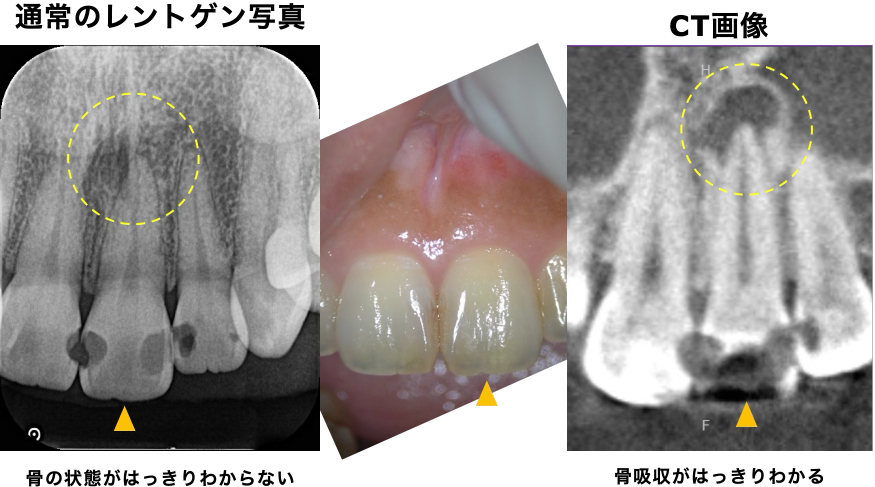

通常のレントゲン写真では根の先の状態は不明瞭でした。おそらく、前医では、神経の検査を的確に行うことが難しかったことと、レントゲンでは根の先の状態の判断に迷ったため、患歯(どの歯が原因か)が断定できなかったと推測されます。

CTを撮影したところ、根の先にはっきりと黒い影(膿・骨の吸収像)が認められ、臨床検査、レントゲン検査から、左上の前歯が原因と確定しました。